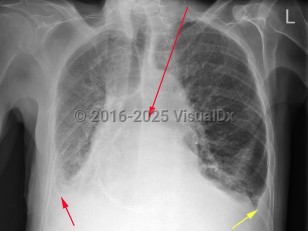

- Airway / Breathing: Often, positive end-expiratory pressure (PEEP) is required via a continuous positive airway pressure (CPAP) or bilevel positive airway pressure (BiPAP) machine for increased work of breathing, hypoxia, or evidence of pulmonary edema on examination or imaging.